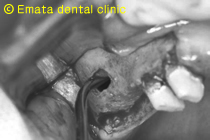

赤い線が上顎洞です。骨造成(サイナスリフトが必要です。)

ピエゾをつかい以前より短時間で確実安全確実に開窓壁の形成、サイナスの挙上ができます。